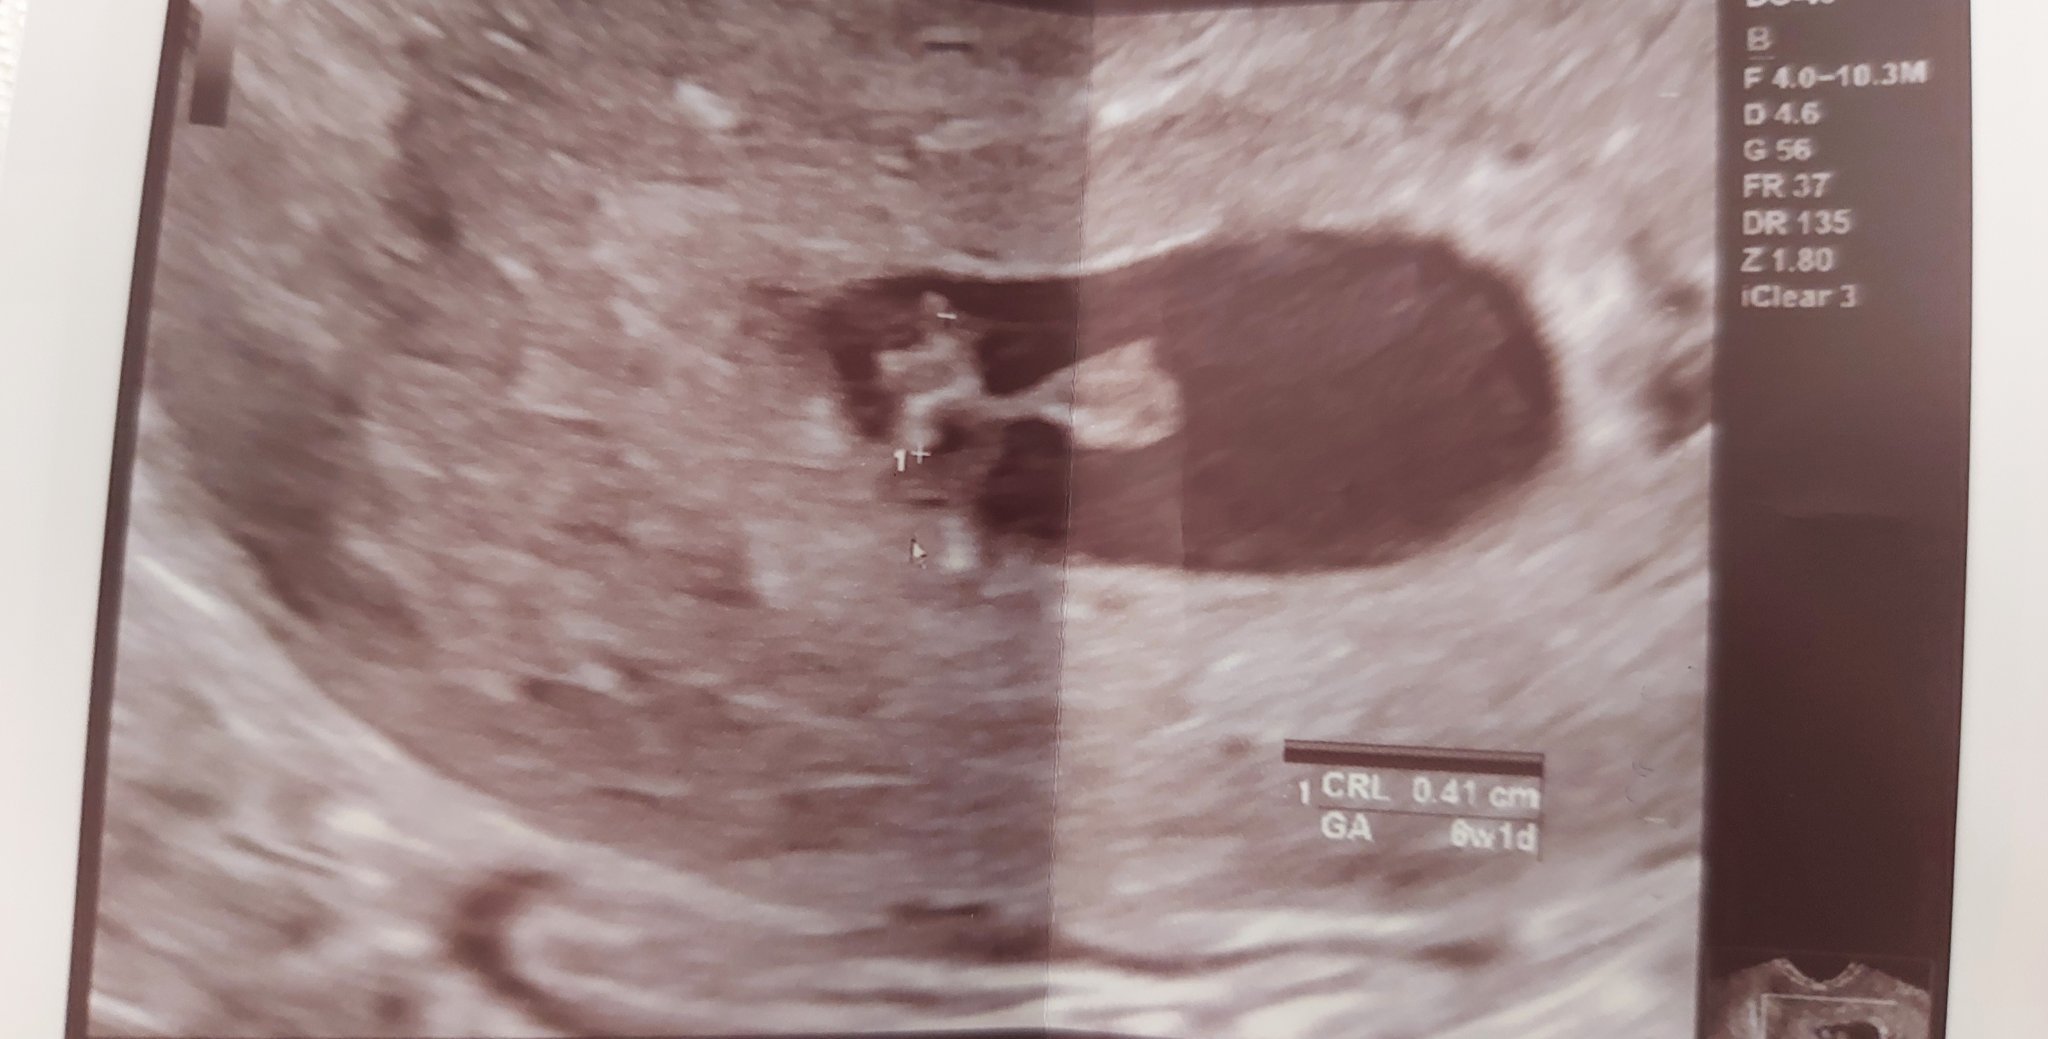

Здравейте, юлски мами. Давам отчет от вчерашния преглед. Точка или точко е пораснал/а видяхме и чухме сърчице. Следващ преглед 26.11. По повод термина и изчислението от калкулатора съм 6+4, а по това, което виждам от снимката на доки(ще прикача) ясно се вижда 6+1. Леко разминаване не е никакъв проблем. Те си знаят хората. Хубав и слънчев ден на всички бъдещи мами 🤗

Здравейте! Безкрайно съм щастлива! Вече имаме жив ембрион с размери. CRL-8,4мм и пулсации. Видях тупкащото сърчице! В 6+5 г.с. Съм ! Аз се разплаках като видях сърчицето как тупка! Няма по-голяма радост от това! Вземаха Ми секрет за микробиология да видим въпроса с течението. За сега всичко е наред и сме на преглед след 2 седмици!